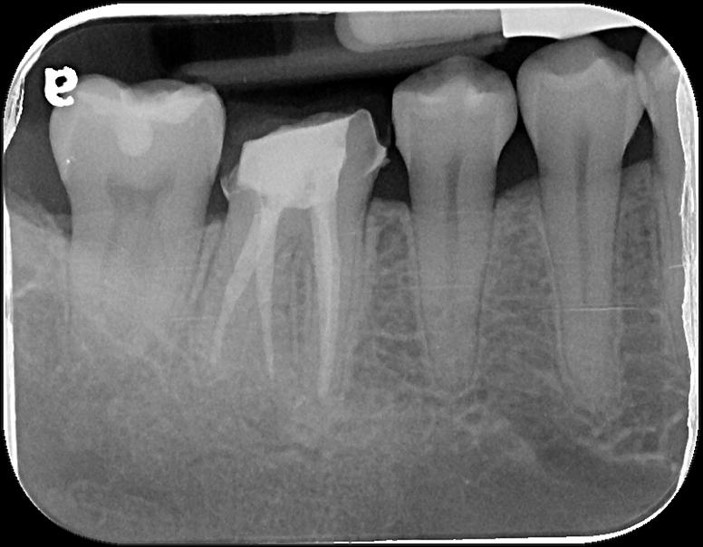

治療前,根管已治療過

顯微根管治療